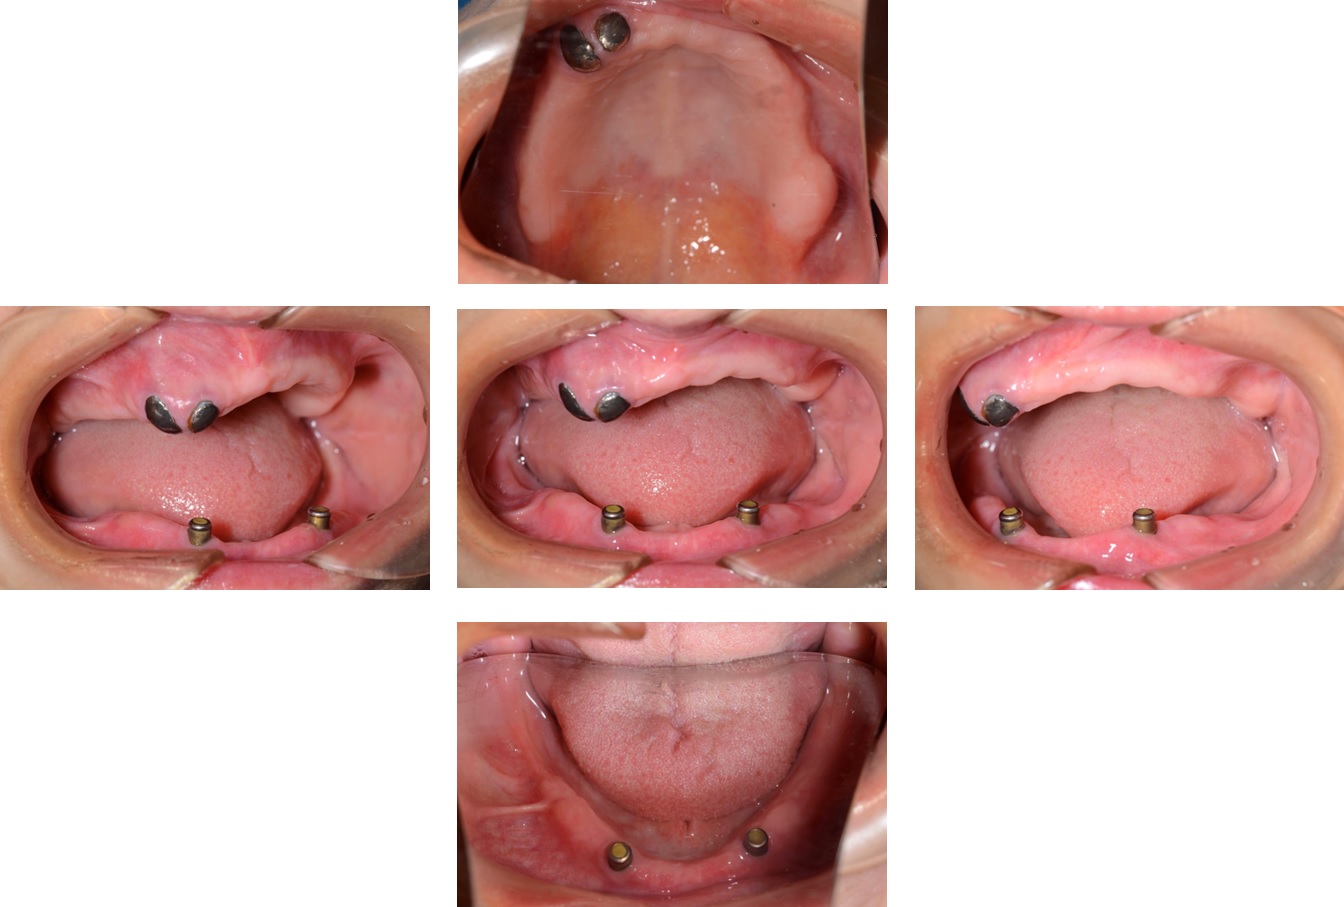

旧義歯装着時

入れ歯を装着した状態

上顎の入れ歯は割れていたが、入れ歯安定剤を用いて、ご自身で修理をしたとのことでした。

また、前歯にはクラスプが設定されており、審美的な配慮がなく、患者さまは不満を訴えていました。

入れ歯を外した状態

下の歯は虫歯があり、グラグラな状態でしたが、上顎の歯は揺れは認められませんでした。

下顎の歯ぐきは細く、痩せていたため、強い力では噛みにくいことが考えられました。

新義歯非装着時

上下の義歯を外した状態です。

上顎の根面板(根だけ残している状態)と下顎のアタッチメント周囲はご自身でのメインテナンスと歯科医院での定期的なメインテナンスで管理していきます。